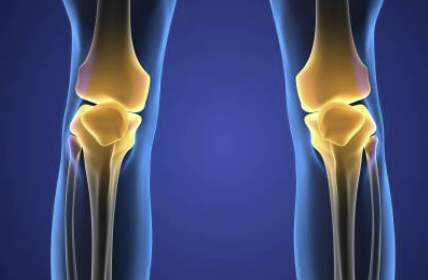

십자인대 파열 증상 원인 치료방법 등 십자인대 파열에 관한 정보 알아보도록 하겠습니다. 십자인대는 무릎 관절 내부에 있는 크로스밴드로, 대퇴골과 정강이 사이를 가로지르며 무릎 관절을 유지하는 중요한 역할을 합니다. 하지만 외상이나 나이, 비만 등으로 인해 손상되면 무릎 통증, 불안정성, 굽힘 및 펴짐 제한 등의 증상이 나타납니다. 큰 부상이 없어도 반복적인 무릎 부하나 체중 등에 의해 부담을 받는 경우에도 손상이 생길 수 있으며, 무릎 관절을 지지하는 인대 중에서는 가장 높은 부상률을 가지고 있습니다. 처치하지 않으면 불안정한 무릎 관절이 발생하며, 장기적으로는 무릎 관절염이나 연골손상 등을 초래할 수 있기 때문에 증상이 나타나면 적절한 치료가 필요합니다.

십자인대는 무릎 관절을 안정시키는 중요한 조직 중 하나로, 만일 십자인대가 파열된다면 무릎을 움직이는데 큰 문제가 발생할 수 있습니다. 십자인대 파열의 초기 증상으로는 무릎 부위에 갑작스러운 통증이 느껴지는 경우가 많습니다. 이어서 부종이나 출혈, 무릎 관절 부근 부분의 압력감 또한 느껴질 수 있습니다. 걷거나 달리는 등 일상적인 활동이 어려워지며, 무릎 관절 근육이 약해져 근육 긴장도나 균형감각 또한 떨어지는 경우가 있습니다. 만약 십자인대 파열이 심한 경우, 무릎 관절이 불안정해져 엉덩이나 무릎 부상의 위험성이 높아질 수 있습니다. 이로 인해 무릎 관절이 불균형하게 움직이면서 연골이 마모되고 골관절염 등의 문제가 발생할 가능성이 높아집니다.